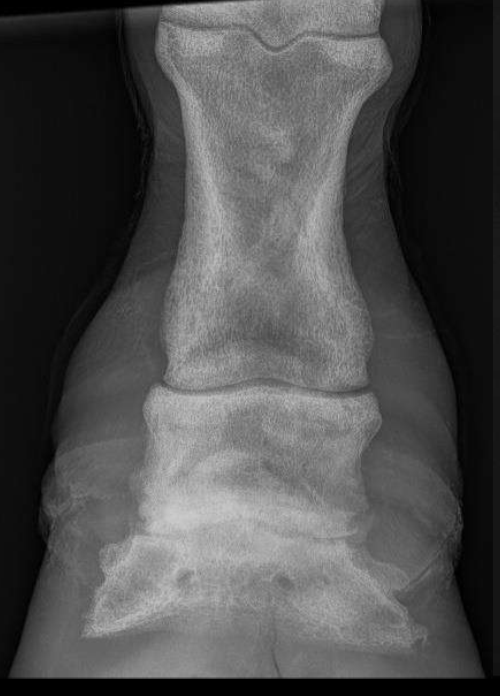

Osteopenia (decreased overall density, more trabeculae)